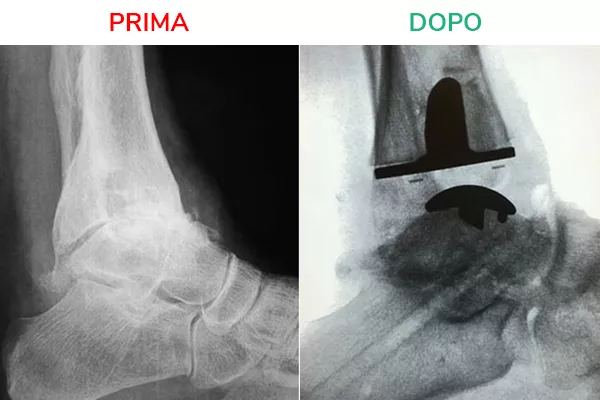

Radiografia in movimento

La radiografia in movimento mostra lo spazio articolare ripristinato e la distanza tra tibia e astragalo. Il movimento risulta fluido e scorrevole, simile a quello fisiologico. Il risultato che si deve ottenere al termine dell’intervento di Protesi di Caviglia è la normale mobilità della caviglia in flesso-estensione.